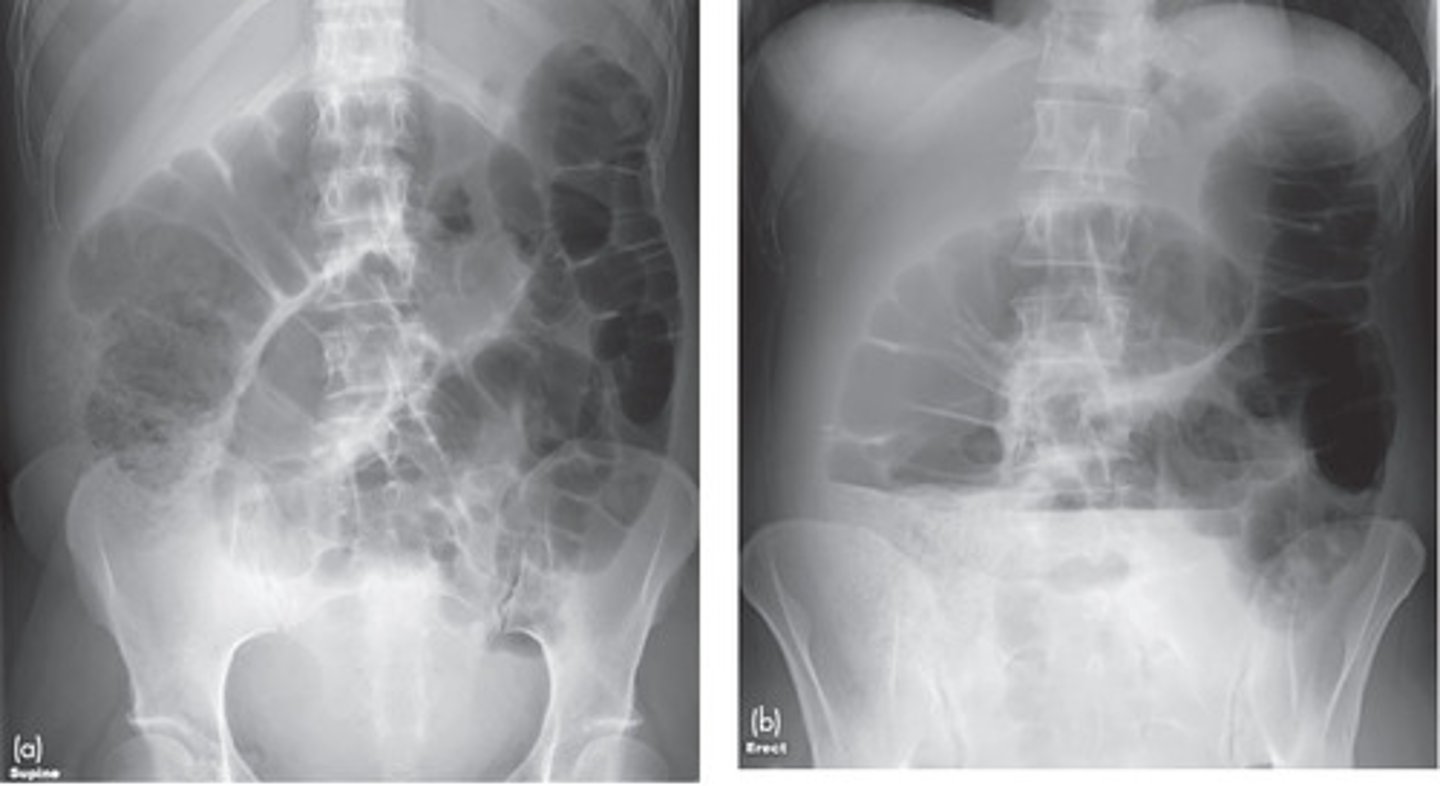

acute abdominal series

supine abdomen/KUB/scout - bowel gas pattern, calcifications, masses

upright abdomen - free air, air-fluid levels

normal gas patterns

air in stomach, 2-3 loops of air in non-dilated small bowel, air in rectosigmoid, no free air in diaphram, liver displaces gas, no fluid or dilation of colon

colon

normally distended bowel loops, air fills lumen completely, haustra visible

small intestine

located centrally, valvulae markings extend across lumen from one wall to another

ileus

paralysis of smooth muscle of intestines, inability of intestinal wall to perform peristalsis, bowel sounds decreased or absent

generalized adynamic ileus

entire bowel is aperistaltic, swallowed air dilates and fluid fills most loops of both small and large bowel

on imaging entire bowel is air-containing and dilated, air fluid levels, gas in rectum or sigmoid

small bowel obstruction

lesion obstructs lumen, proximal to transition point bowel loops become dilated with air, distal to transition point bowel loops become decompressed, no air in rectosigmoid

SBO imaging

X-Ray shows multiple dilated bowel loops, "step ladder appearance", no or little gas in colon/rectum